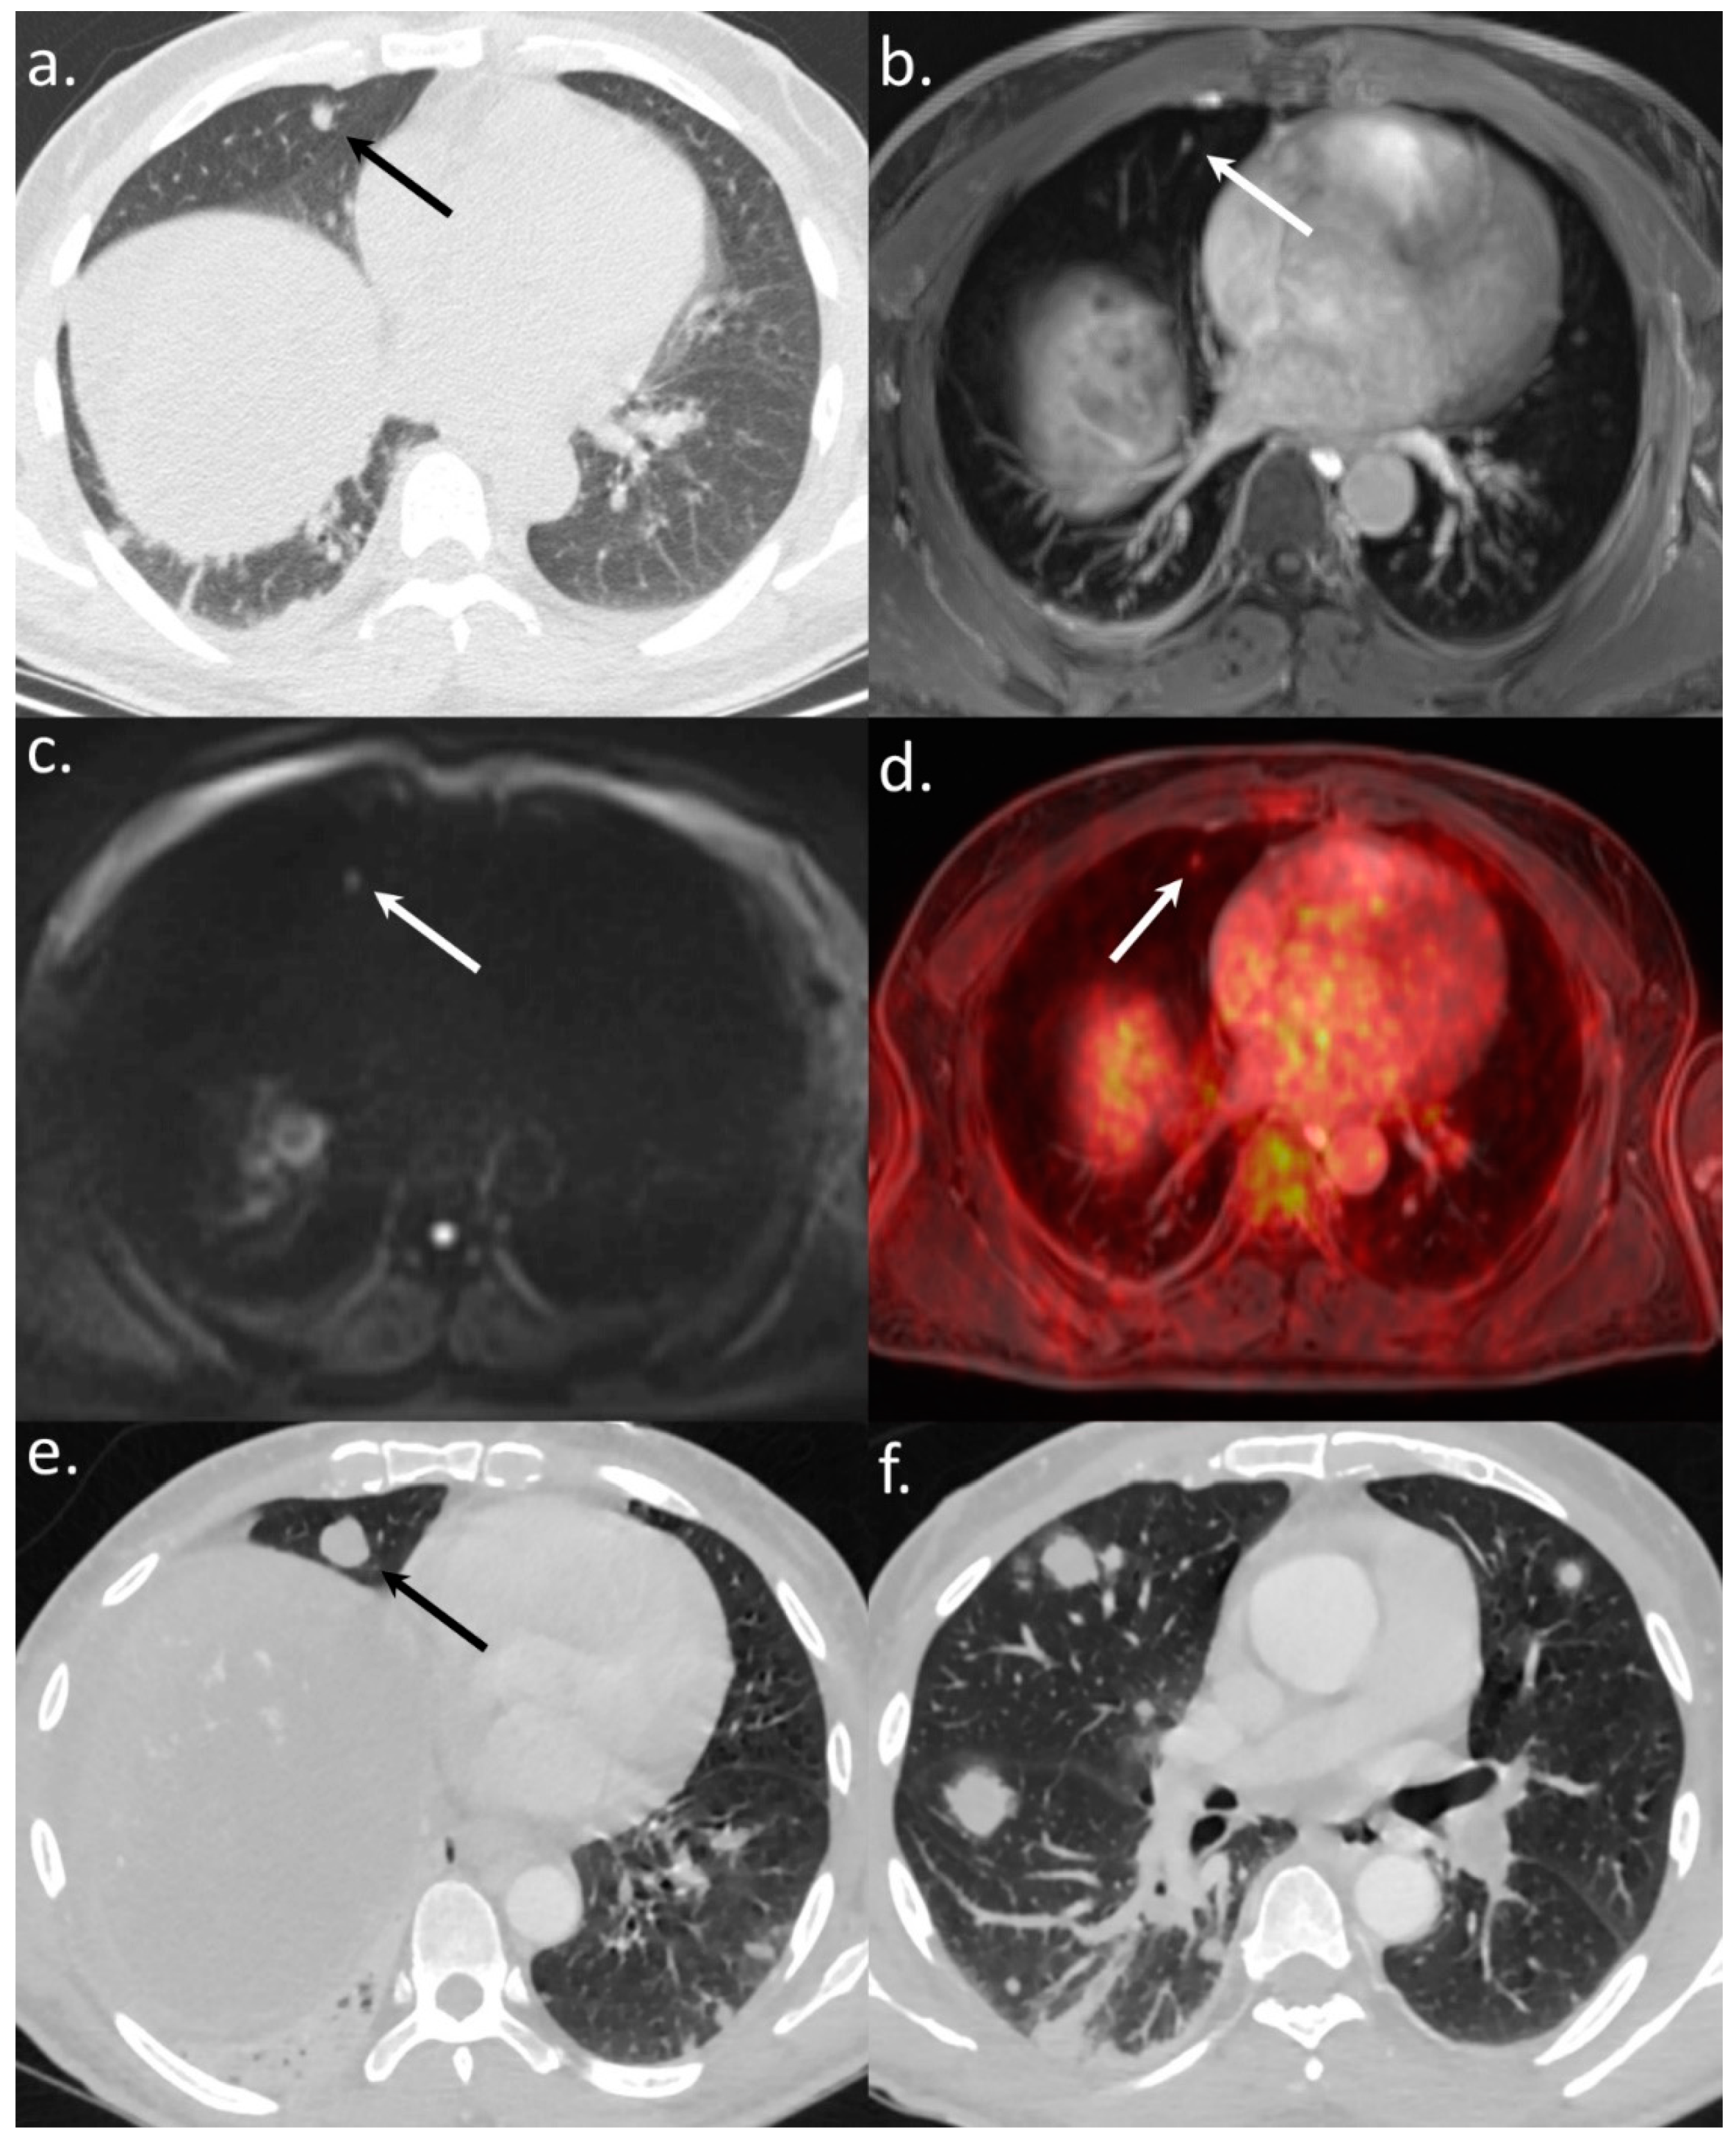

Figure 6. An 82-year-old BCLC A patient referred for a WB-PET/MRI before liver surgery for HCC. The CT-CAP showed an 11 mm large round-shaped pulmonary nodule (a). The nodule was also visible on the morphologic MRI sequence (b). There was no diffusion restriction (c) and no 18F-FDG hypermetabolism (d) leading to the exclusion of lung metastasis. Surgery was performed and, on CT followup performed two years after the WB-PET/MRI (e), the nodule remained stable without the appearance of additional lesions.

In three BCLC stage A patients imaged before surgical resection, three lesions suspected of metastasis on the CT-CAP/liver MRI (Figure 5 and Figure 6) were correctly invalidated on the WB-PET/MRI owing to their hypometabolism on the PET.